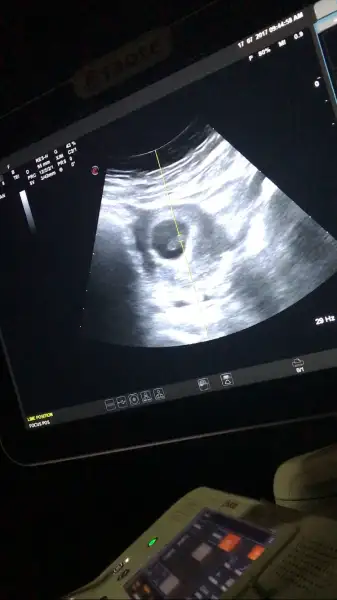

Kizlar resim eklemeden soyleyeym .simdi kese yuvarlaksa kiz elips gibi fasulye gibiyse erkek .bebek kesenin solunda duruyosa kiz sagindaysa erkek .birde bebeği karninizin solunda hissediyorsanız kıZ saginda hissediyosaniz erkek.bu forumda gordum bu teoriyi kizda hepsi tuttu .tuttu dyen cok var ama tutmadı diyende var

Nasıl resim ekleyeceğiz ama ya

IMG_3001.webp

Cevaplanin yannda dosya yükle var